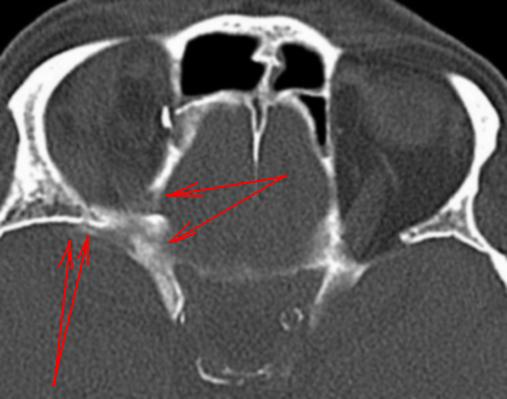

Желтые стрелки - это фрагменты костных отломков? Красная стрелка - это перелом или нет. А откуда появился фрагмент (он потолще всех) - зеленая стрелка.

Помеченное красными стрелками можно также расценивать, как нарушение целостности костной ткани?

Желтые стрелки - это оскольчатый перелом, зеленая - костный отломок, сместившийся в орбиту. Там, где красные стрелки переломов нет. По нижней стенке орбиты инфраорбитальная борозда, переходящая в инфраорбитальное отверстие, открывающееся кпереди ниже нижнего края орбиты.